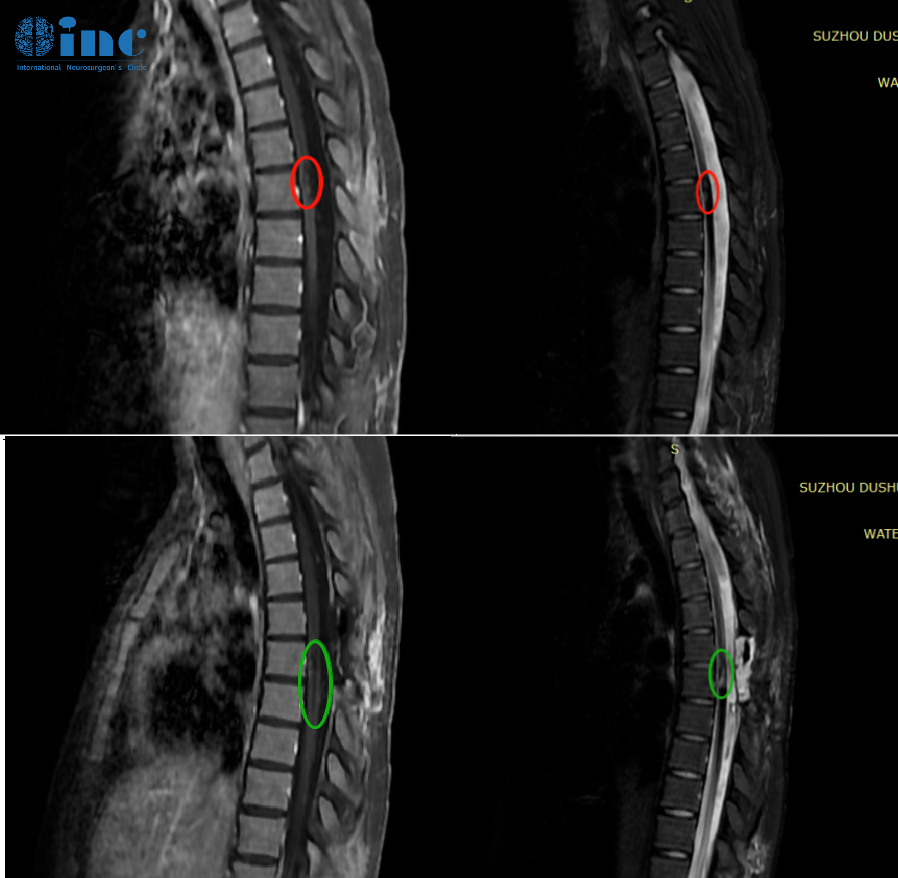

▼术前术后MRI影像对比

辅助检查:胸髓MRI

诊断:胸髓(T6)内占位:海绵状血管瘤;椎管扩大减压术后

2、海绵状血管瘤偏腹侧,位置较深,脊髓表面病灶显现不明显,术中超声辅助定位